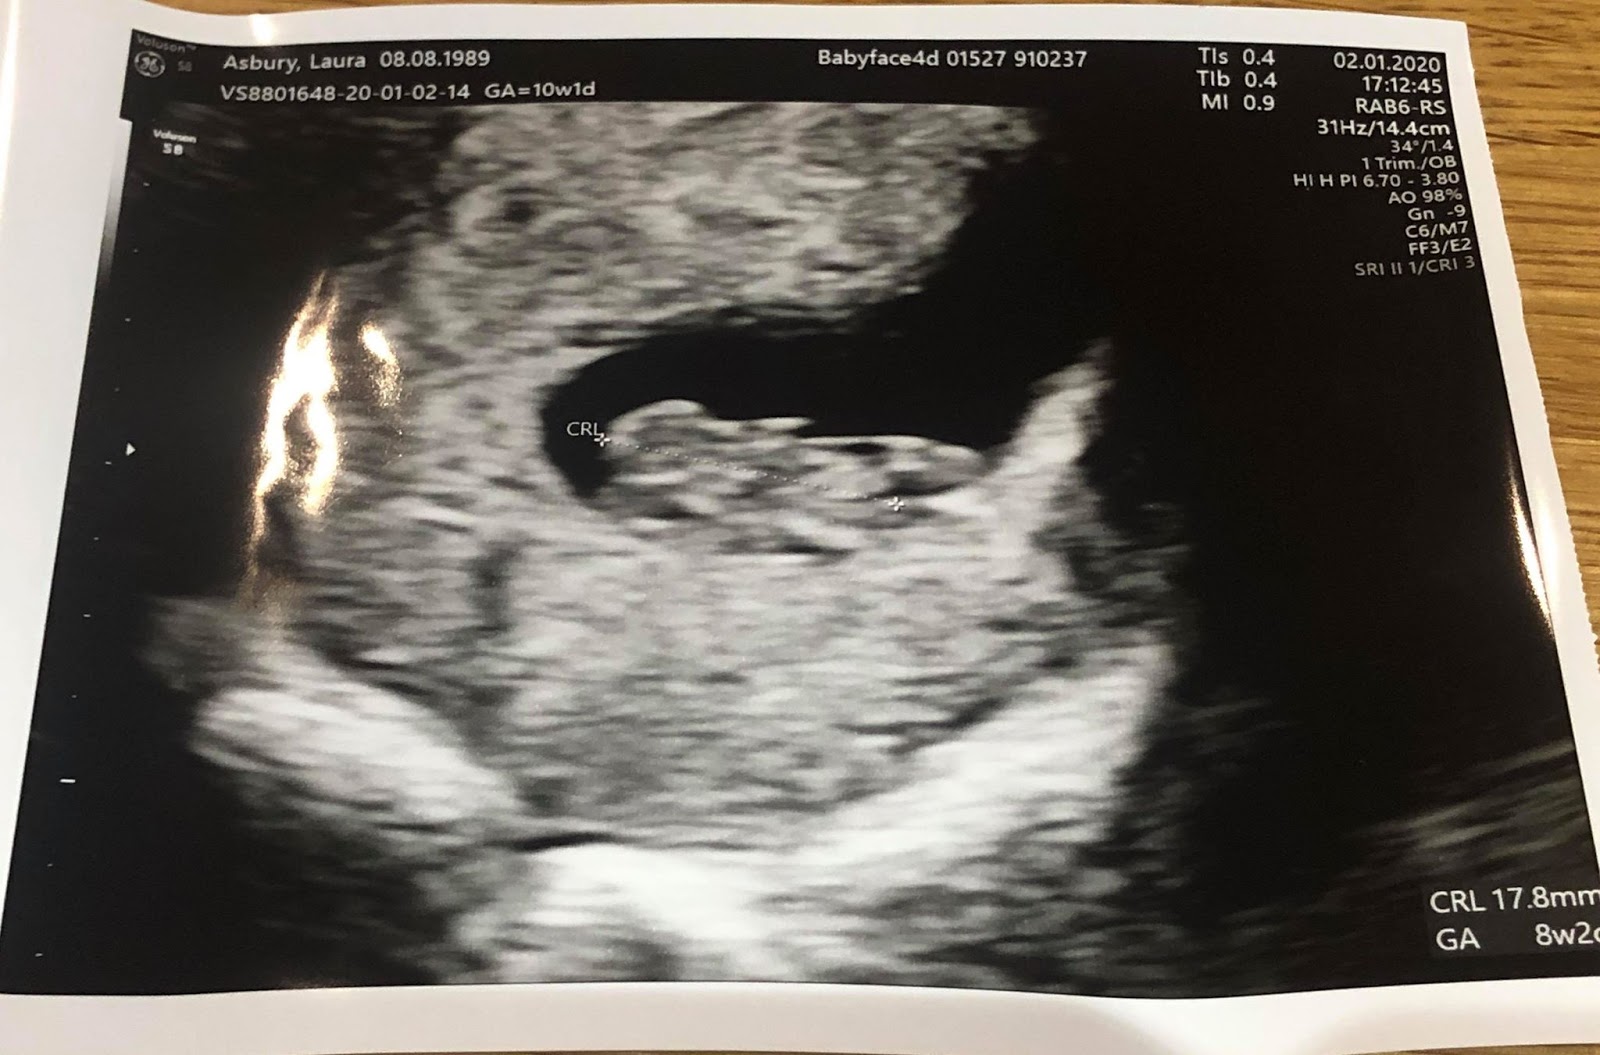

Eight weeks into a pregnancy is the most common time to have a first ultrasound , also called the " dating " scan, as one of the main purposes is to determine gestational age . Gestational age is determined using the baby's size and offer an accurate estimation of when the baby was conceived .

12 weeks . Between 8 - 12 weeks of pregnancy is a good time for a dating scan . A 2-D image of a baby at about 8-9 weeks . Small arms are becoming visible, sticking out slightly in the middle of the baby . The wavy line near the bottom of the image measures the heartbeat which in this baby is 188 beats per minute .

What will I see on the ultrasound ? At 7 weeks gestation a pregnancy sac should be seen within the uterus . Within this sac will be an embryo, heart motion and yolk sac should be visible . Approaching 8 weeks , early brain formation is identified with a black space in the head called the rhombencephalon .

What Can You Expect to See at the Eighth Week Ultrasound ? This is what the embryo looks like at 8 weeks : The eyes would have migrated from the sides to the front . The embryo would measure 2 .3 cms from crown to rump . The outer ears would be starting to form . Your baby can move his elbows . The fingers look like tiny buds .